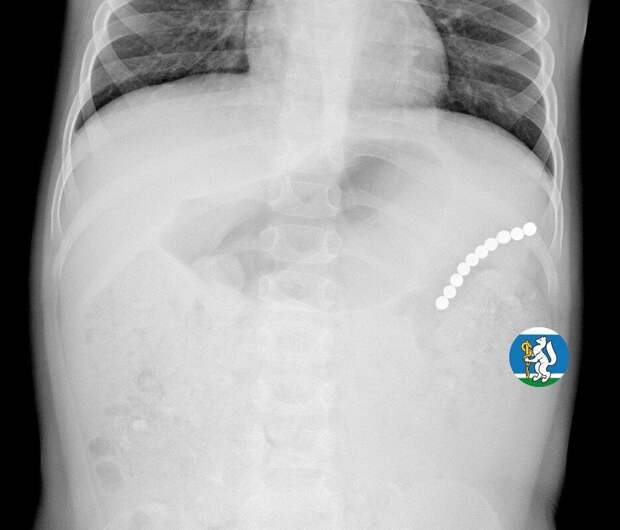

Девочка рассказала родителям о плохом самочувствии, и те показали ее врачам. Медики направили пациентку на рентген грудной клетки.

Благодаря обследованию специалисты обнаружили в проекции желудка цепочку магнитов, соединенных между собой. Ребенку сразу же госпитализировали и оказали помощь."Для минимизации риска осложнений удаление инородных тел было проведено интраоперационно. В ходе вмешательства дежурная бригада врачей извлекла 10 магнитных шариков, цепочка которых в длину составила 5 сантиметров", - рассказал детский хирург ДГКБ №9 Андрей Чукреев.